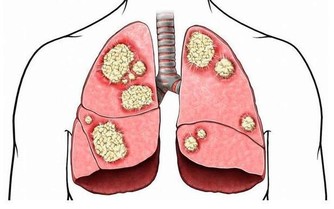

當患者未能及時接受治療時,癌細胞會擴散到身體的其他組織和器官,例如肝臟。